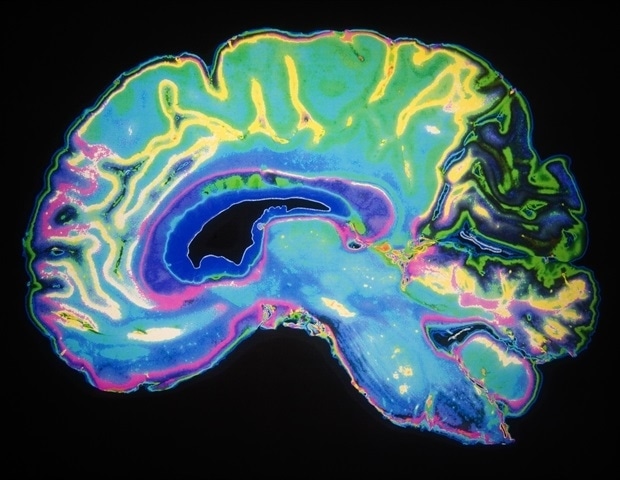

מדענים מאוניברסיטת הרפואה של דרום קרוליינה מדווחים ב עֲצָבוֹן שהם חשפו דרך לשחזר מסלול מוחי מוחלש באופיואידים במודל פרה-קליני. עם